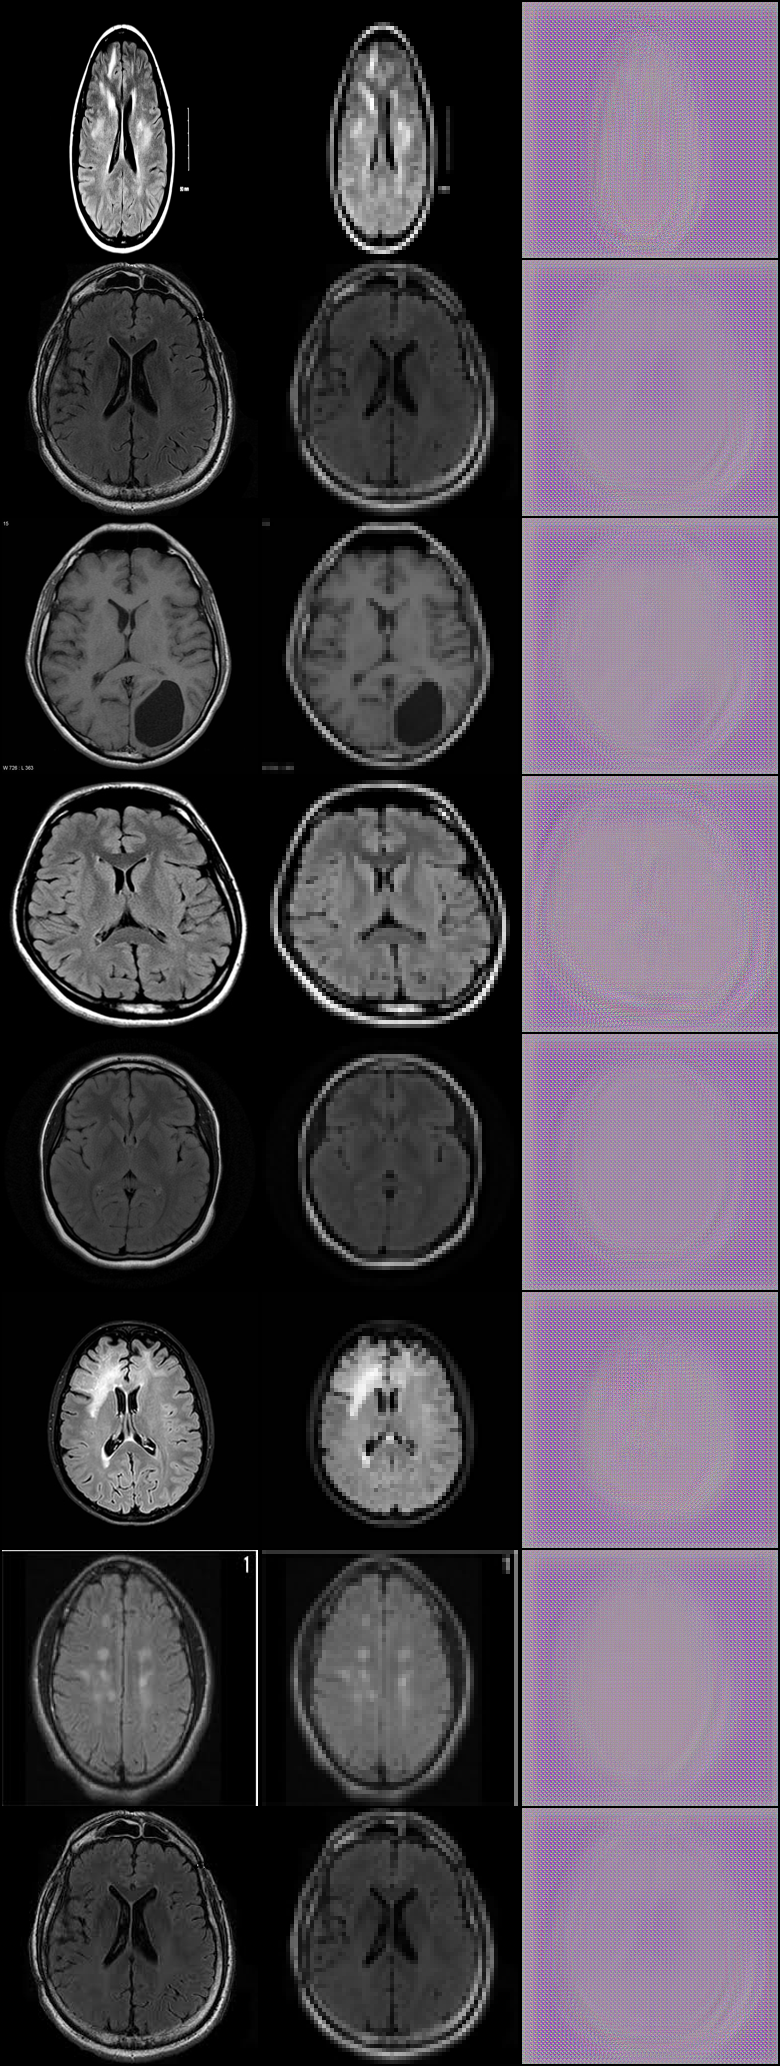

Overcoming The Data Barrier

Data quality remains the top barrier when it comes to using machine learning to extract valuable insights. Data engineering problems also pose a significant problem, such as data being siloed, lack of talent to connect disparate data sources, and not being fast enough to process data in a meaningful way. An innovative solution known as Generative Adversarial Networks, or GANs for short, are an approach to generative modeling using deep learning methods, such as convolutional neural networks. Generative modeling is an unsupervised learning task in machine learning that involves automatically discovering and learning the regularities or patterns in input data in such a way that the model can be used to generate or output new examples that plausibly could have been drawn from the original dataset.

Prototype

To test the speed, practicality, efficiency, and cost of quantum-accelerated ML as well as its usefulness in precision medicine, we have devised two prototypes written in Python. The concise, expressive, and dynamic nature of the Python language makes it well suited for prototyping tasks. The first prototype notebook uses the GAN to artificially manufacture images for model training. The second prototype notebook is a hybrid quantum-classical neural network that utilizes the generated image set along with the pre-existing data for model training and evaluation. To demonstrate the practicality and ease of use of this model, we developed a Wix website with Velo developer mode. This site would act as a doctor and patient portal for doctors to input brain MRIs and predict brain tumor presence, and allow patients to easily view test results.

Data

The original dataset we used for our project can be found in GitHub at https://github.com/PerceptiLabs/Brain-Tumors.